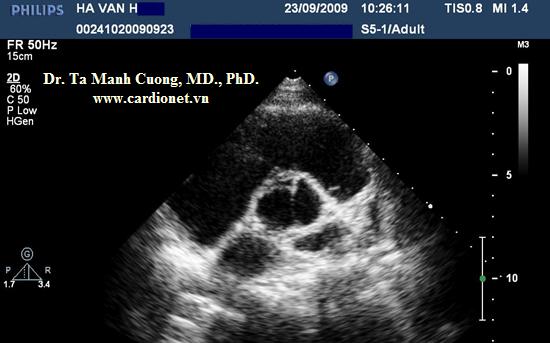

Một bệnh nhân khác: Hở chủ nhẹ, động mạch chủ chỉ có hai lá van:

- Trong thì tâm trương: